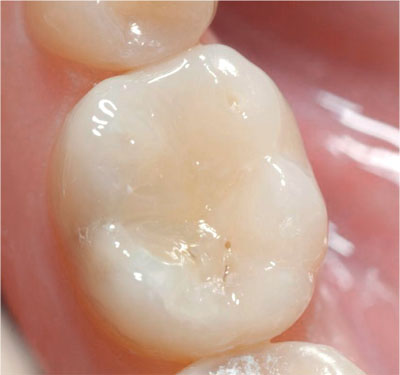

As a consequence of increased dental awareness in society, coupled with improvements in dietary and oral hygiene practices, many more patients, particularly younger patients, are now presenting with fewer and smaller lesions of caries than in the past (Figs 1-1 and 1-2). Such patients expect minimally interventive procedures, preferably using techniques that are described as “aesthetic” or “tooth coloured” (Fig 1-3). This, in association with commercial developments in composite resin materials and associated bonding technologies and lingering concerns over the safety of dental amalgam, has driven an increase in the placement of posterior composite restorations in general dental practice. For example, a survey of United Kingdom general dental practitioners in 2001 revealed, far from limiting the placement of composite to small cavities in premolar teeth, that almost one-half of general dental practitioners placed composite resin restorations in load-bearing cavities in molar teeth (Figs 1-4 to 1-6).

Fig 1-3 A recently placed composite restoration in the occlusal surface of a mandibular first molar.